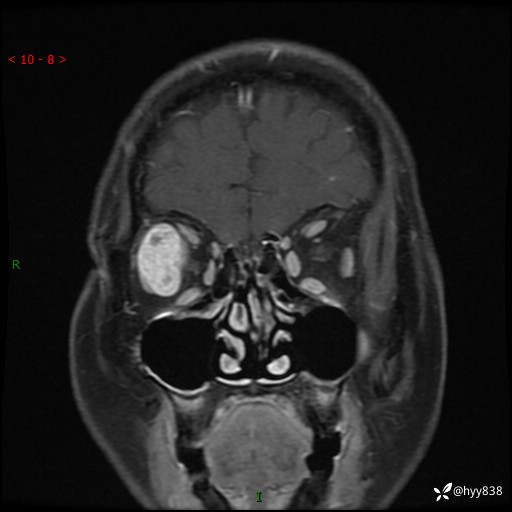

老年女性,右眼球突出1月。说说鉴别诊断,看谁第一个秒---(有结果)

主诉:发现右眼球突出1月余

简要病史:患者于1月前无明显诱因发现右眼球突出,偶感磨痛、眼胀,无视力下降,无头痛,恶心呕吐等不适。10天前就诊于当地县人民医院就诊,完善头颅ct检查,诊断为右侧眼眶肿物,建议患者上级医院进一步治疗,患者因个人原因拒绝。拟行手术,来我院就诊,门诊行相关检查后以“右眼眼眶肿物”收入院。 患病以来,患者精神饮食睡眠尚可,大小便如常、体重无明显改变。

辅助检查:MRI

临床诊断:眼眶肿物

眼眶MRI平扫+增强